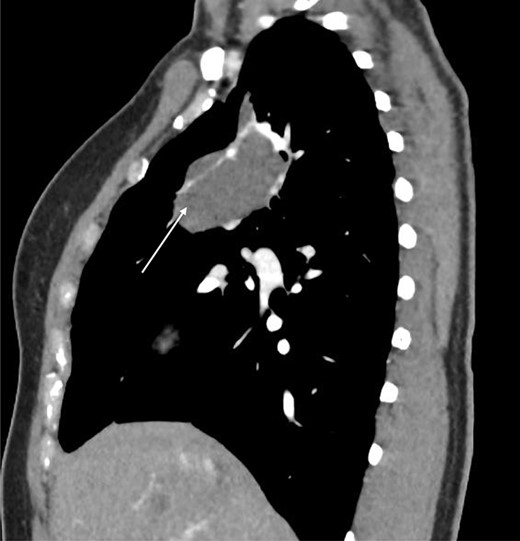

Computed tomography (CT) scans demonstrated a well-demarcated right-sided 5.5 × 2.6 cm paramediastinal solid mass, with associated atelectasis of the RUL (Figs 1 and 2). Traversing this segment, a large venous tributary of the azygous vein was identified (Fig. 2).

Sagittal CT scan demonstrating pulmonary sequestration in the right upper lung lobe (arrow).